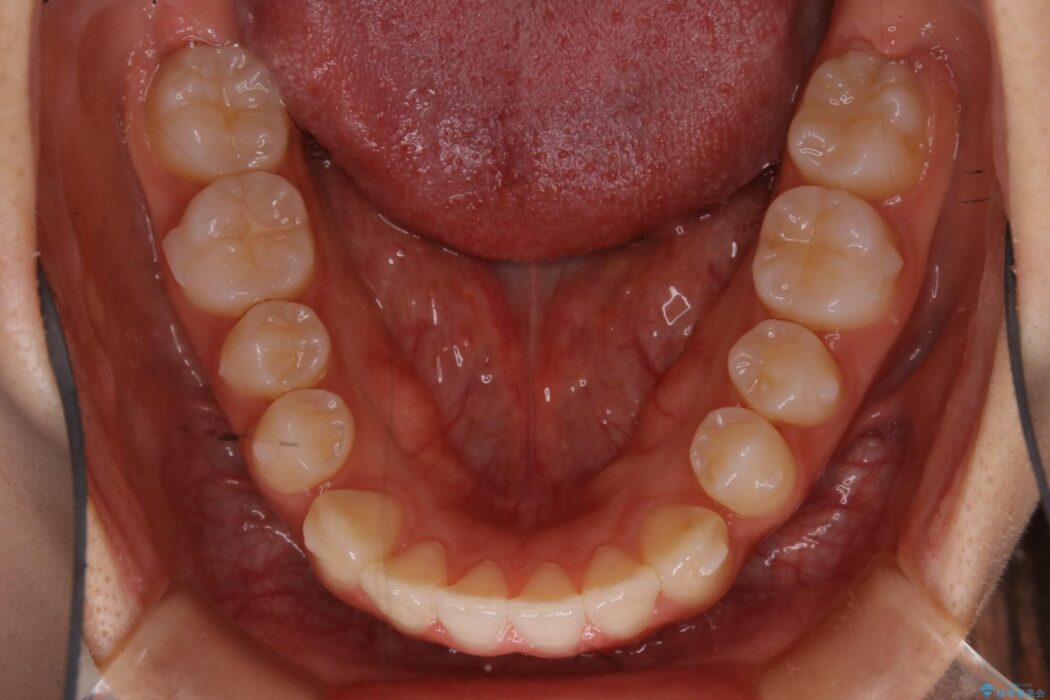

治療後について

正常な噛み合わせ位置へと改善したことにより奥歯で噛みしめることができ、加えて見た目も受け口から変わって大変ご満足いただけました。